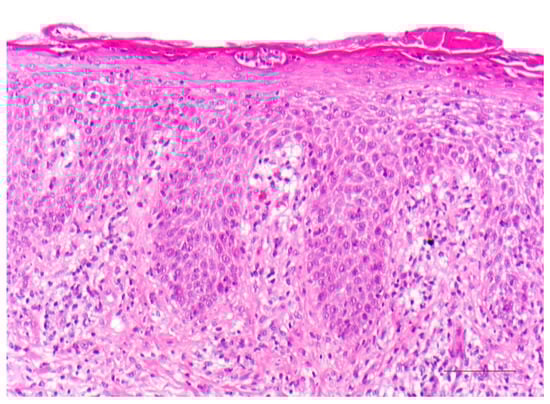

5. Keratinopathic Ichthyosis

5.1. Histology